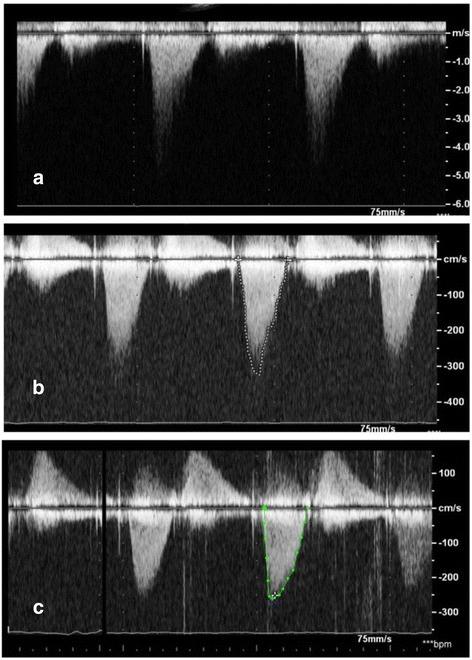

We present a case that displays the unique therapeutic challenges of treating a patient who developed both LVOT obstruction and mitral PVL after undergoing surgical aortic and mitral valve replacement (MVR). We also describe the use of alcohol septal ablation and albumin-glutaraldehyde (BioGlue) for septal ablation to percutaneously treat the patient's LVOT obstruction, followed by use of an Amplatzer vascular plug for percutaneous closure of an antero-medial mitral PVL associated with severe regurgitation.